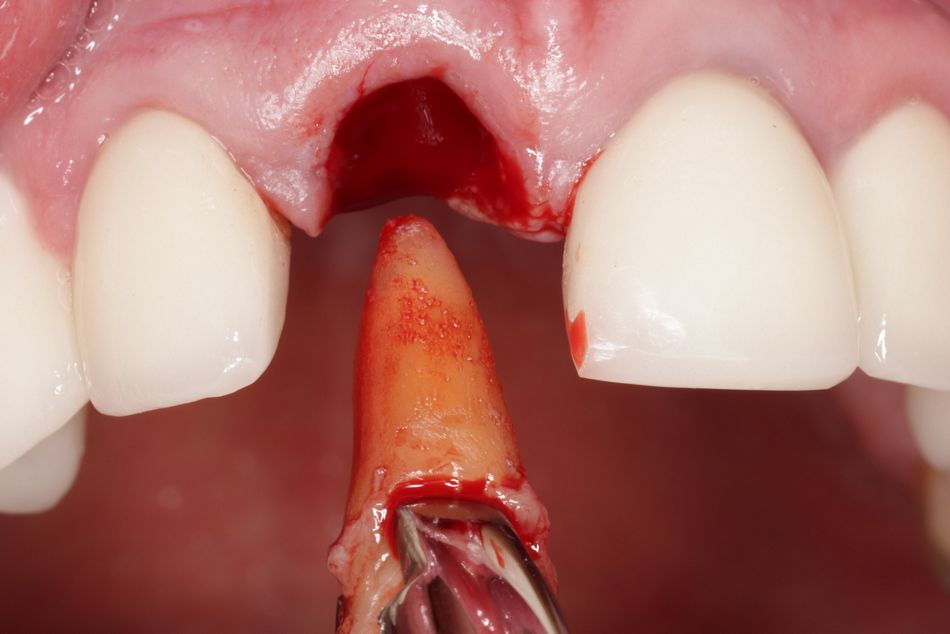

Nach einer präoperativen Planung wurde der frakturierte Zahn 11 behutsam unter maximaler Schonung der Alveolenwände extrahiert (Abb. 6). Die Alveole blieb intakt; Hart- sowie Weichgewebe waren unversehrt. Ein Vorteil der Sofortimplantation ist der direkte Zugang zur Alveole. Es kann lappenfrei gearbeitet werden, die Blutversorgung bleibt erhalten, Narbengewebe (z. B. durch vertikale Entlastungsschnitte) wird vermieden [12, 5]. Das Trauma und die Unterbrechung der Blutversorgung des Knochens durch das Bilden eines Mukoperiostlappens kann eine Resorption des Knochenvolumens begünstigen [13]. Das lappenfreie Vorgehen ist wenig invasiv und bringt in der Regel eine geringe postoperative Belastung für den Patienten mit. Allerdings bedarf es auch implantologischer Erfahrung, da beispielsweise die Sichtverhältnisse eingeschränkt sind.